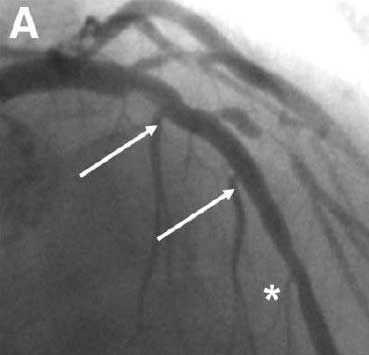

6年前,患者曾因不稳定性心绞痛接受冠脉造影检查,结果显示左前降支(LAD)近段有一严重病变,对角支弥漫性病变,左回旋支完全闭塞。随后于LAD置入1枚3.5×12 mm西罗莫司洗脱支架,置入后造影示支架远端段有轻度不规则(图1星号处),但总体效果良好。尝试再通左回旋支失败。

图1